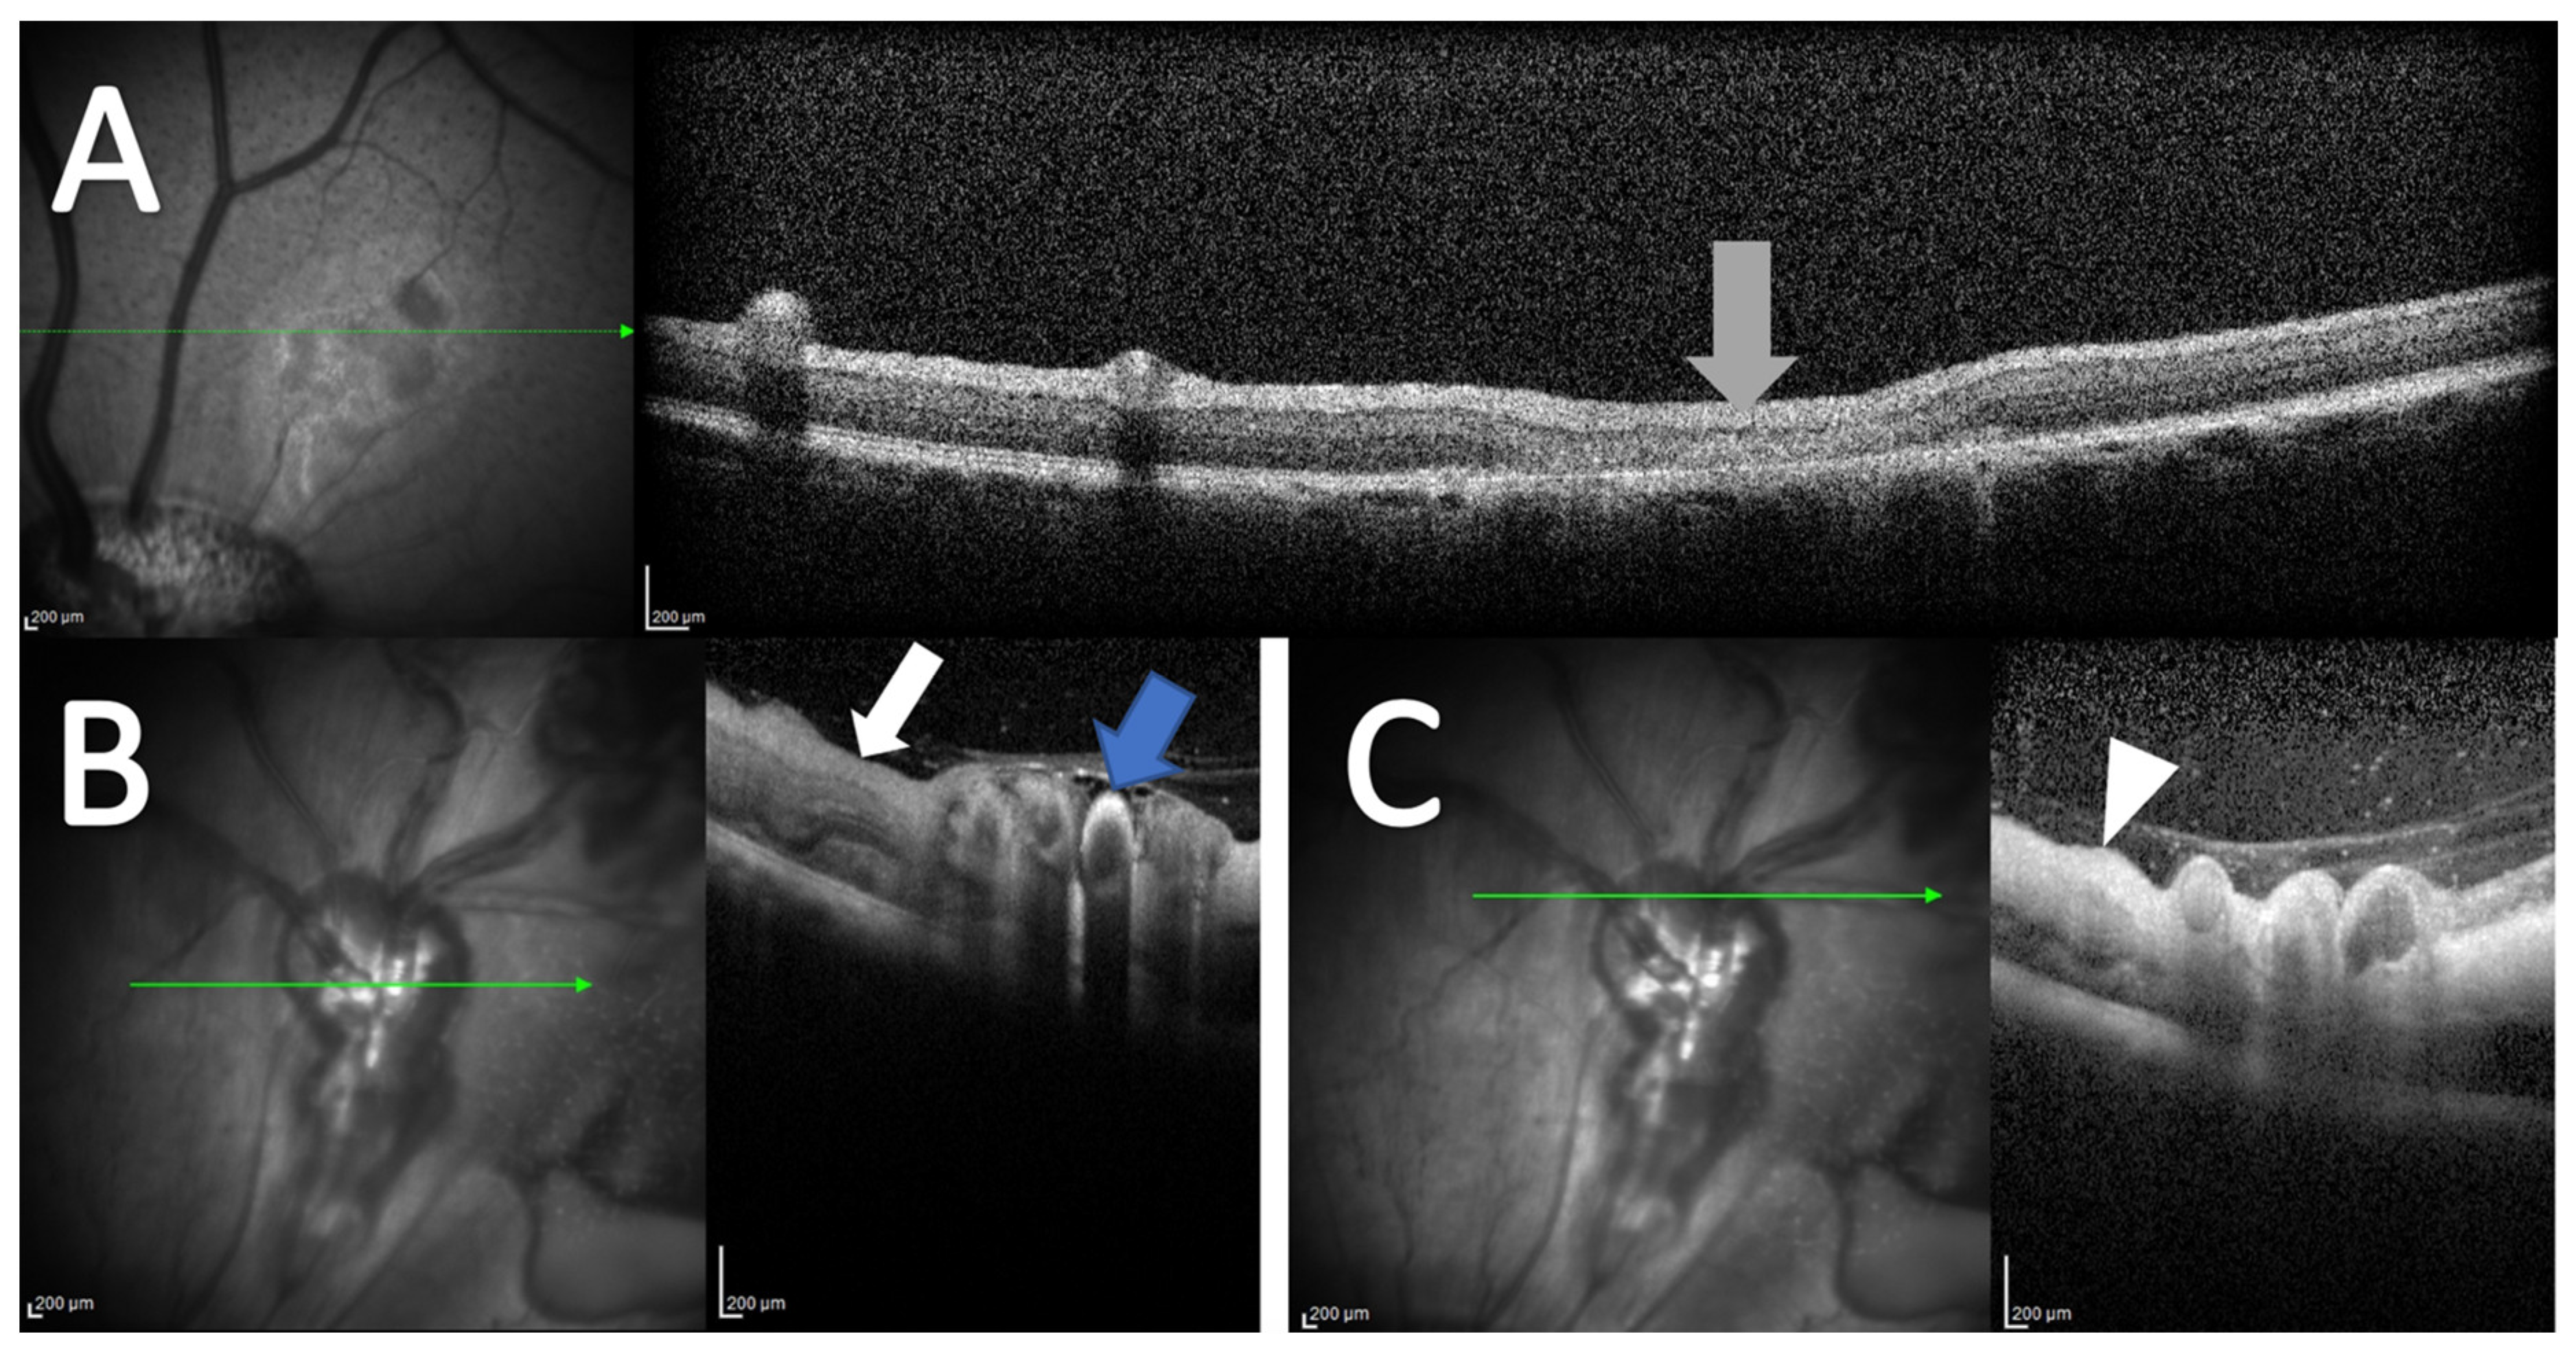

3.3. Optical Coherence Tomography